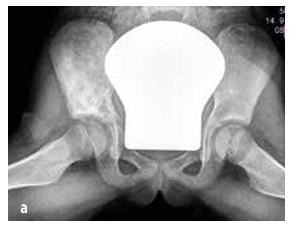

Obrázok č. 4

Klinické nálezy pri septickej artritíde

Septická artritída sa vyskytuje v 50 % prípadov pred dovŕšením druhého roku života a v 75 % prípadov postihuje kĺby dolných končatín (koleno > bedro > členok) (pozri obrázok 4). Osteomyelitída sa najčastejšie lokalizuje v metafýze.

Infekciu kostí alebo kĺbov zvažujeme u detí s náhlym nástupom horúčky, nevysvetliteľným krívaním a/alebo abnormálnym postavením končatiny, odmietaním používať končatinu, obmedzeným rozsahom pohybu, bolesťou pohybového aparátu ± lokalizovanou citlivosťou kĺbu alebo kosti a opuchom so začervenaním (pozri obrázok 4). POZOR: malé deti nedokážu presne lokalizovať bolesť (napr. bolesť vyžarujúca z bedra do oblasti kolena).